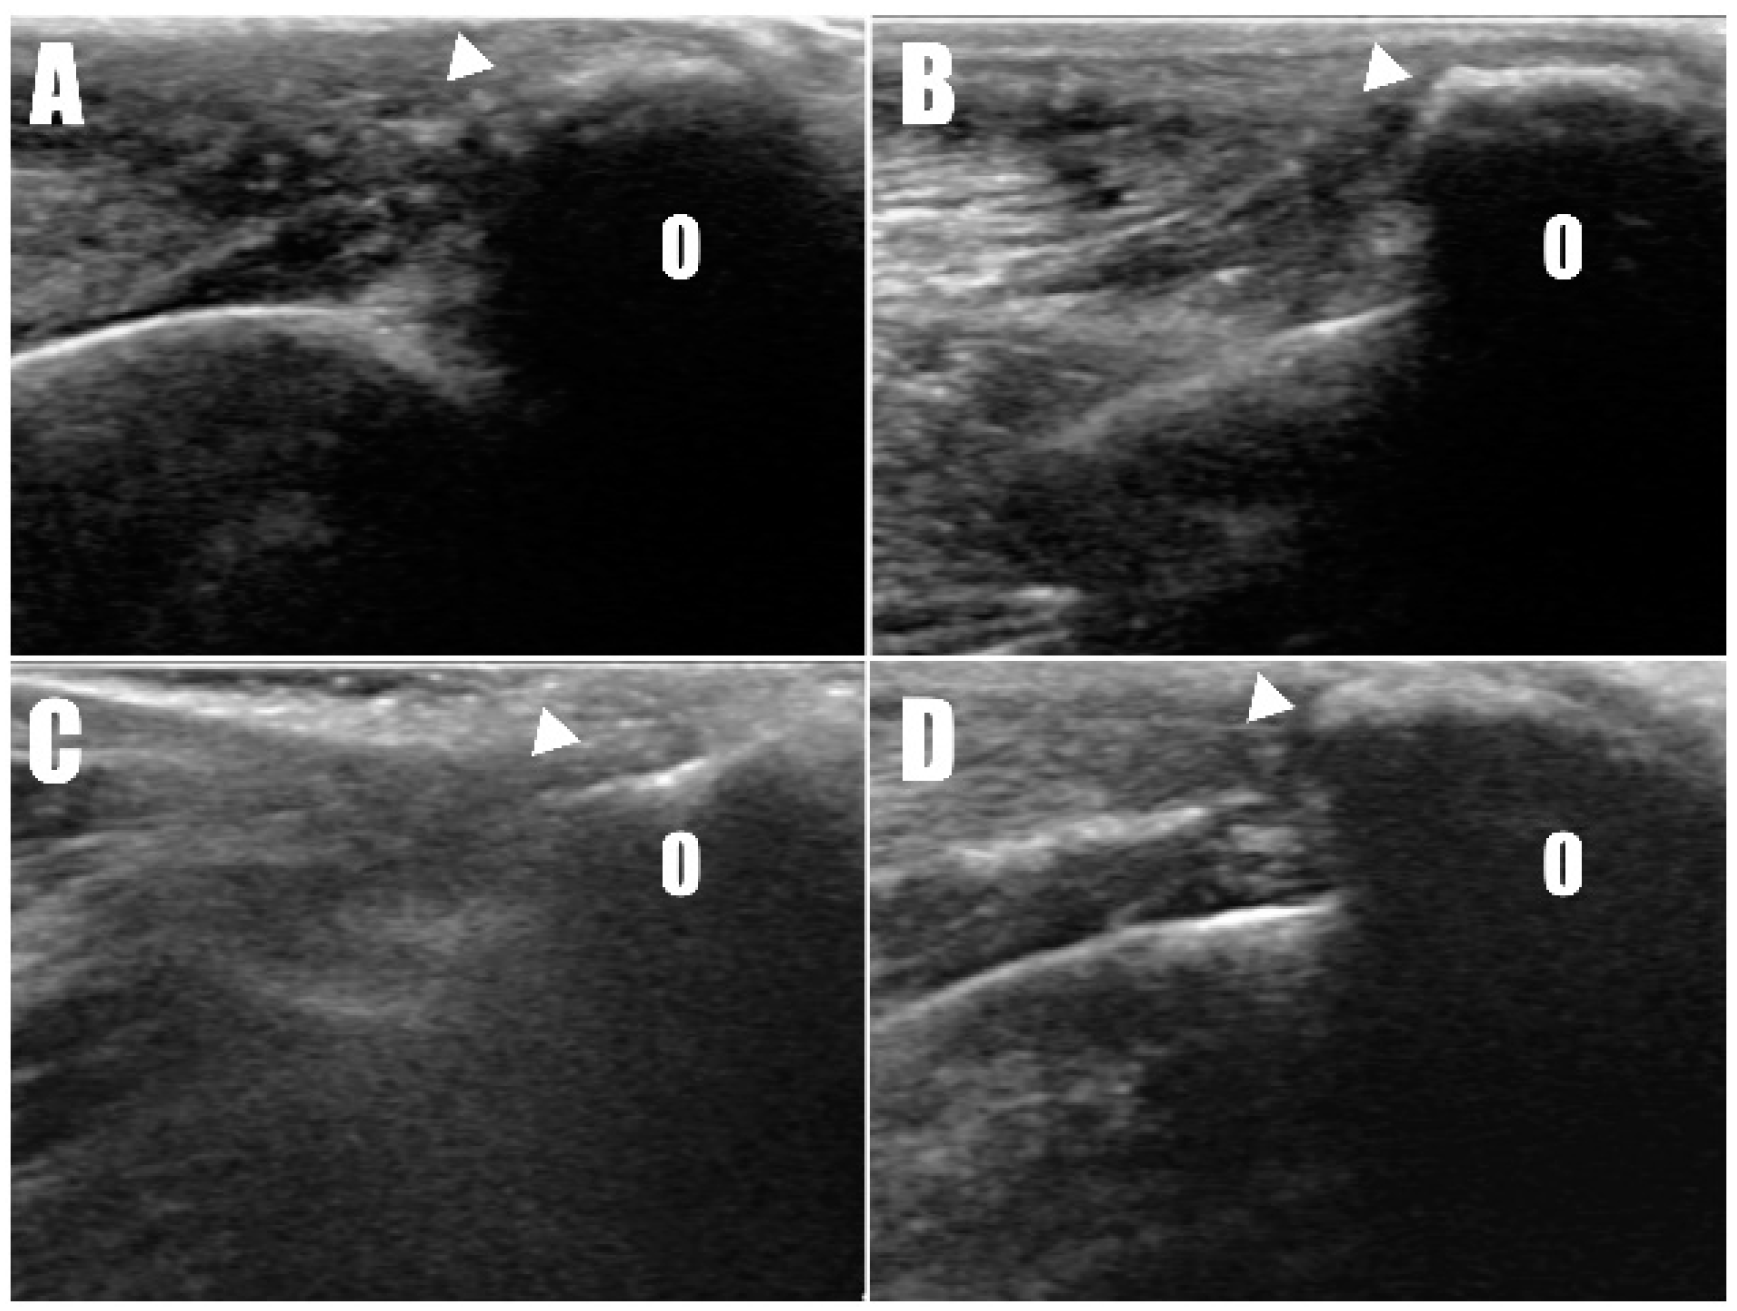

Figure 7. Ultrasound images taken two weeks postoperatively of the (A) right and (B) left forelimbs confirm the attachment of the triceps brachii tendon (arrowhead) to the olecranon (O). Similar findings were observed in the ultrasound images six months postoperatively on the (C) right and (D) left forelimbs.

Postoperative radiographs and ultrasound images (Figure 6) were taken to confirm the position and connectivity (Figure 7) of the tendon on the olecranon. On the right side (Figure 6A), the transverse hole was observed to be close to the caudal cortex, while the remaining bone tunnels were confirmed to have been drilled as intended. For analgesia, remifentanil was continued for three days postoperatively at 0.1~0.3 ug/kg/min with constant rate infusion. The other postoperative therapy including antibiotics (amoxicillin and clavulanic acid, 12.5 mg/kg BID, for 14 days/Clindamycin, 11 mg/kg BID, for 14 days), NSAID (meloxicam, 0.1 mg/kg SID for 14 days), and gastrointestinal protectant (esomeprazole, 1 mg/kg SID for 14 days) were administered.

Radiography (Figure 6C,D) and ultrasonography (Figure 7C,D) six months postoperatively confirmed that the transverse hole of the right side healed without any complications, and the bilateral triceps brachii tendons were well-maintained and attached to the olecranon, with no specific changes in internal echogenicity or echotexture. MRI (Figure 8) showed mild inflammatory changes near the suture knot and fibrotic scar tissue within the tendon but confirmed firm attachment of the tendon to the olecranon. Three years following the surgery, the patient exhibited no signs of functional loss (Video S2) or pain, confirming the long-term success of the treatment. The owner expressed satisfaction with the clinical outcomes.